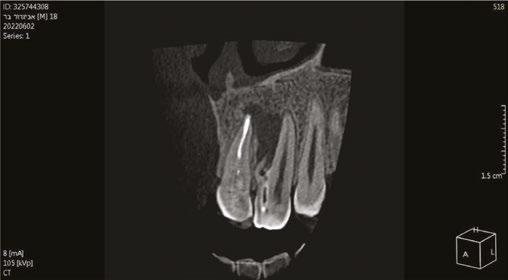

Case 1: Pre-op and diagnosis: A 68-year-old female presented with localized vestibular swelling buccal to tooth No. 30. No. 30 had been symptomatic for a few days, but the swelling started to alarm the patient and caused her to seek treatment. Upon evaluation, No. 30 was diagnosed as necrotic pulp with acute apical abscess. Two treatment options were discussed with the patient: 1) Tooth No. 30 non-surgical root canal therapy or 2) Tooth No. 30 extraction. The patient elected tooth No. 30 non-surgical root canal therapy (NSRCT). A pre-op Small FOV CBCT revealed a heavily calcified pulp chamber and calcified canals and a radix entomolaris. The CBCT revealed PARL’s at the apex of the mesial, distal, and radix entomolaris roots with the lesion extending coronally into the furcation. The patient was advised before treatment that this would be a very challenging case, and No. 30 NSRCT would be given a guarded prognosis, but she chose to proceed with No. 30 NSRCT. Treatment: No. 30 NSRCT, the patient was anesthetized with 68 mg Lidocaine with 0.034 mg EPI via IAN and 68 mg Septocaine with 0.017 mg EPI via buccal infiltration. Rubber dam isolation was utilized, and access was prepared through the PFM crown. 4 canals were located and then immediately after identification of the canal orifices, a platform was created with Soundseal, and the GentleWave Cleanflow handpiece was utilized to help break up the calcified tissue and negotiate each canal, alternating between a pathfile to slowly negotiate the coronal half of the canals and then running the GentleWave CleanFlow Procedure Instrument for 30-40 seconds to remove the accumulated debris. By alternating between files and the CleanFlow with GentleWave, all 4 canals were negotiated to length, and patency was achieved. The final working lengths were between 23 mm-24.5 mm for all 4 canals. All canals were instrumented to a Master Apical File of 20/.04 and obturated with high-flow BC Sealer. By utilizing the GentleWave and High-Flow BC Sealer, the apical delta of the distal root was cleaned, disinfected, and obturated in ways that would not have been possible with traditional endodontic therapy. Post-op: The patient was called 24 hours after treatment and reported she was pain-free, the swelling had reduced, and she was doing well.

Figure 1: CBCT scan of the tooth demonstrating the radiolucent lesion surrounding the DI and extending to the apex of the central incisor Figures 2A-2D: 2A. Periapical radiograph of the dens. 2B. Hedstrom file in the invagination. 2C. The obturated enamel lining of the invagination with BC putty. 2D. Healing of the periapical lesion in the 1-year follow-up